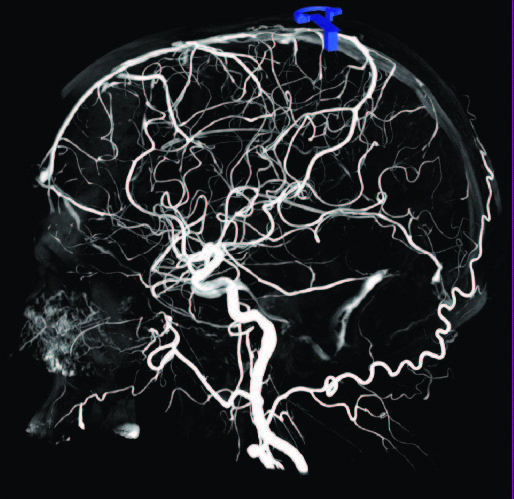

Рис. 1 (а-г). Церебральная ПДКТ-артериография бассейна правой общей сонной артерии, демонстрирующая возможность визуализации артерий диаметром 0,5 мм

Рис. 1а. Реконструкция всего артериального русла после проведения ПДКТ в режиме 20sDCT Head (Siemens Healthineers, Германия) с введением 60 мл контрастного препарата со скоростью 2 мл/с (в течение 30 с) и задержкой сканирования 10 с

Рис. 1б. Визуализация правой центральной артерии сетчатки глаза диаметром 0,5 мм в режиме MIP (тонкие срезы) у того же пациента

Рис. 1в-г. Визуализация той же артерии и дренирующих вен в косых проекциях (MIP) с использованием более толстых срезов.